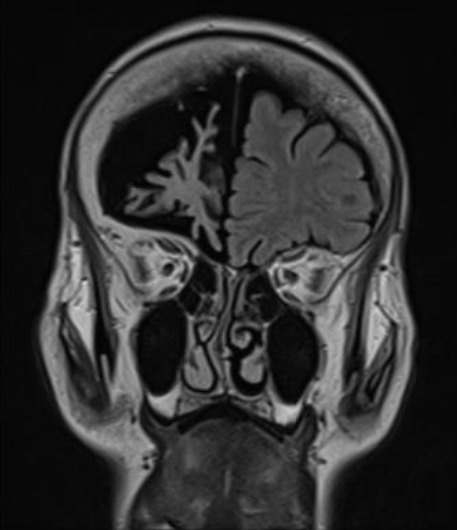

IRM cérébrale, coupe coronale. Le scanner cérébral montre une atrophie hémisphérique droite non connue, une lacune thalamique gauche et une surcharge athéromateuse des carotides.